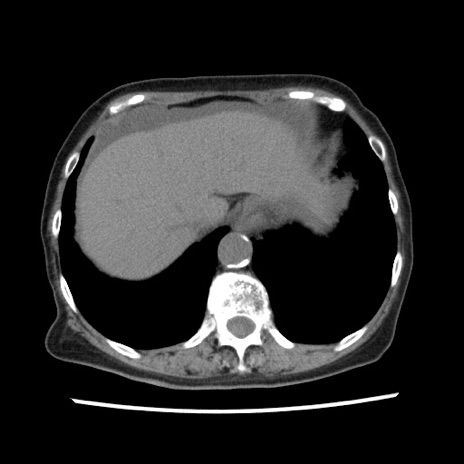

症例1(横断像)

【症例】80歳代女性

【主訴】腹痛

【現病歴】8時間前から腹痛あり来院。

【既往歴】糖尿病、脂質異常症、子宮体癌にて子宮全摘術

【身体所見】意識清明・会話良好だが腹痛で苦悶様、全腹部にわたって反跳痛と圧痛あり

【データ】WBC 13600、CRP 0.14、LDH 224、CK 90